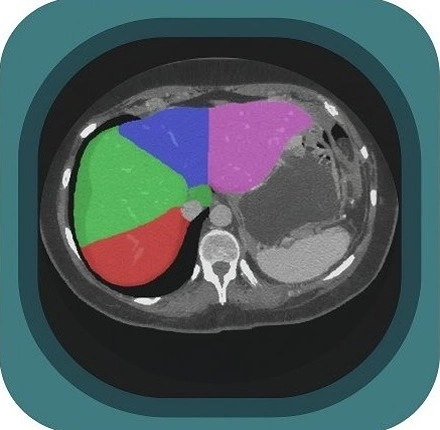

Explore full-body CT anatomy in 3 planes. Our high-resolution, carefully labelled images reveal micro-anatomy—ideal for radiologists, radiographers and surgeons.